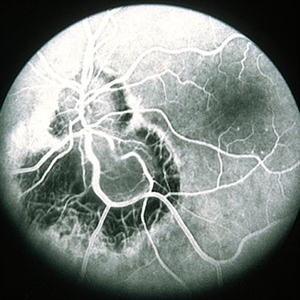

Ocular Toxocariasis slide 2

Ocular Toxocariasis slide 2

Oct 22 2012 by Ronald C. Gentile, MD

The fold of the retina was dry and cord like.

Photographer: The New York Eye & Ear Infirmary Department of Medical Imaging

Condition/keywords: ocular toxoplasmosis